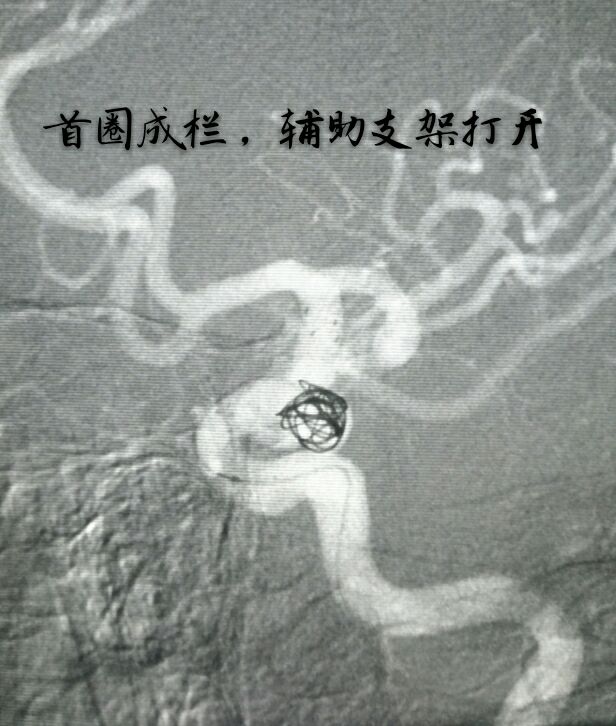

病例十:老年男性患者,间断性头痛1年,DSA示左侧颈内动脉后交通段动脉瘤,后交通动脉从瘤颈部发出

支架打开,首圈完美成栏